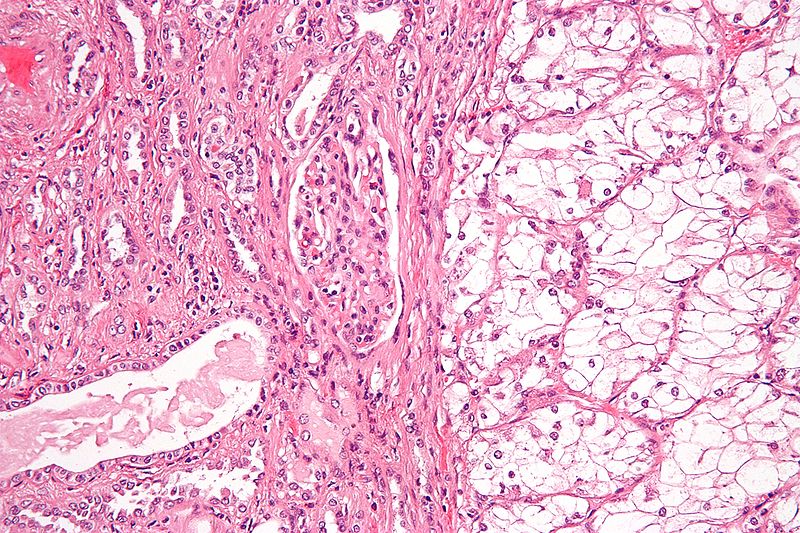

Angiomyolipoma

Angiomyolipoma is a disorder where benign kidney tumors develop.

Angiomyolipoma a tumor made up of blood vessels, smooth muscle, and adipose tissue.